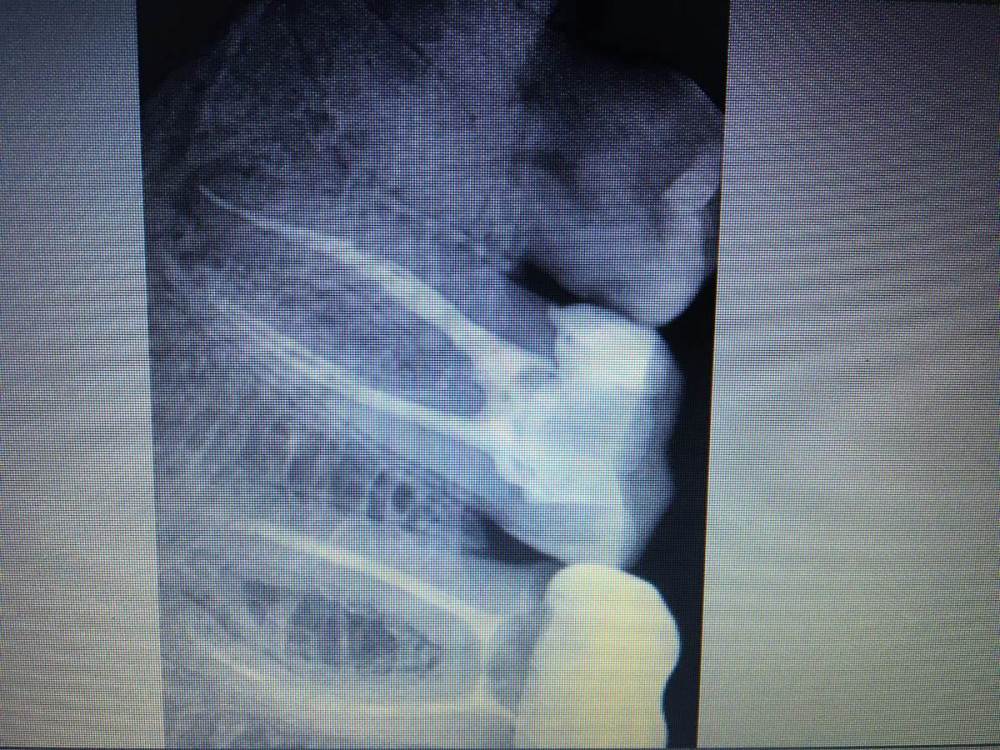

В_2021 Опубликовано 28 сентября, 2021 Поделиться Опубликовано 28 сентября, 2021 В мае зуб (7-ка) депульпирован и запломбирован, где-то в июле начал побаливать при надкусывании (сначала по утрам), в августе другой врач после своего рентгена сказал, что недопломбирован канал, но "автор" стоит на своем - недопломбировка в пределах допустимого, переделывать "не вижу смысла", выписал нимисил и амоксиклав на три дня, рентген - его (сентябрь). (Еще "автор" иногда делает плохие рентгены - сразу после лечения пытался демонстрировать мне снимок, на котором вершины корней не были видны вообще. Не знаю, здесь все видно или нет.) Антибиотик - по ощущениям, безрезультатно. Вроде уже что-то стало слегка "отзываться" на горячее (6-ка, но не факт). Лучше перепломбировать канал где-нибудь или продолжать антибиотик?? Ссылка на комментарий

red_butler Опубликовано 30 сентября, 2021 Поделиться Опубликовано 30 сентября, 2021 требуется повторное лечение корневых каналов Ссылка на комментарий